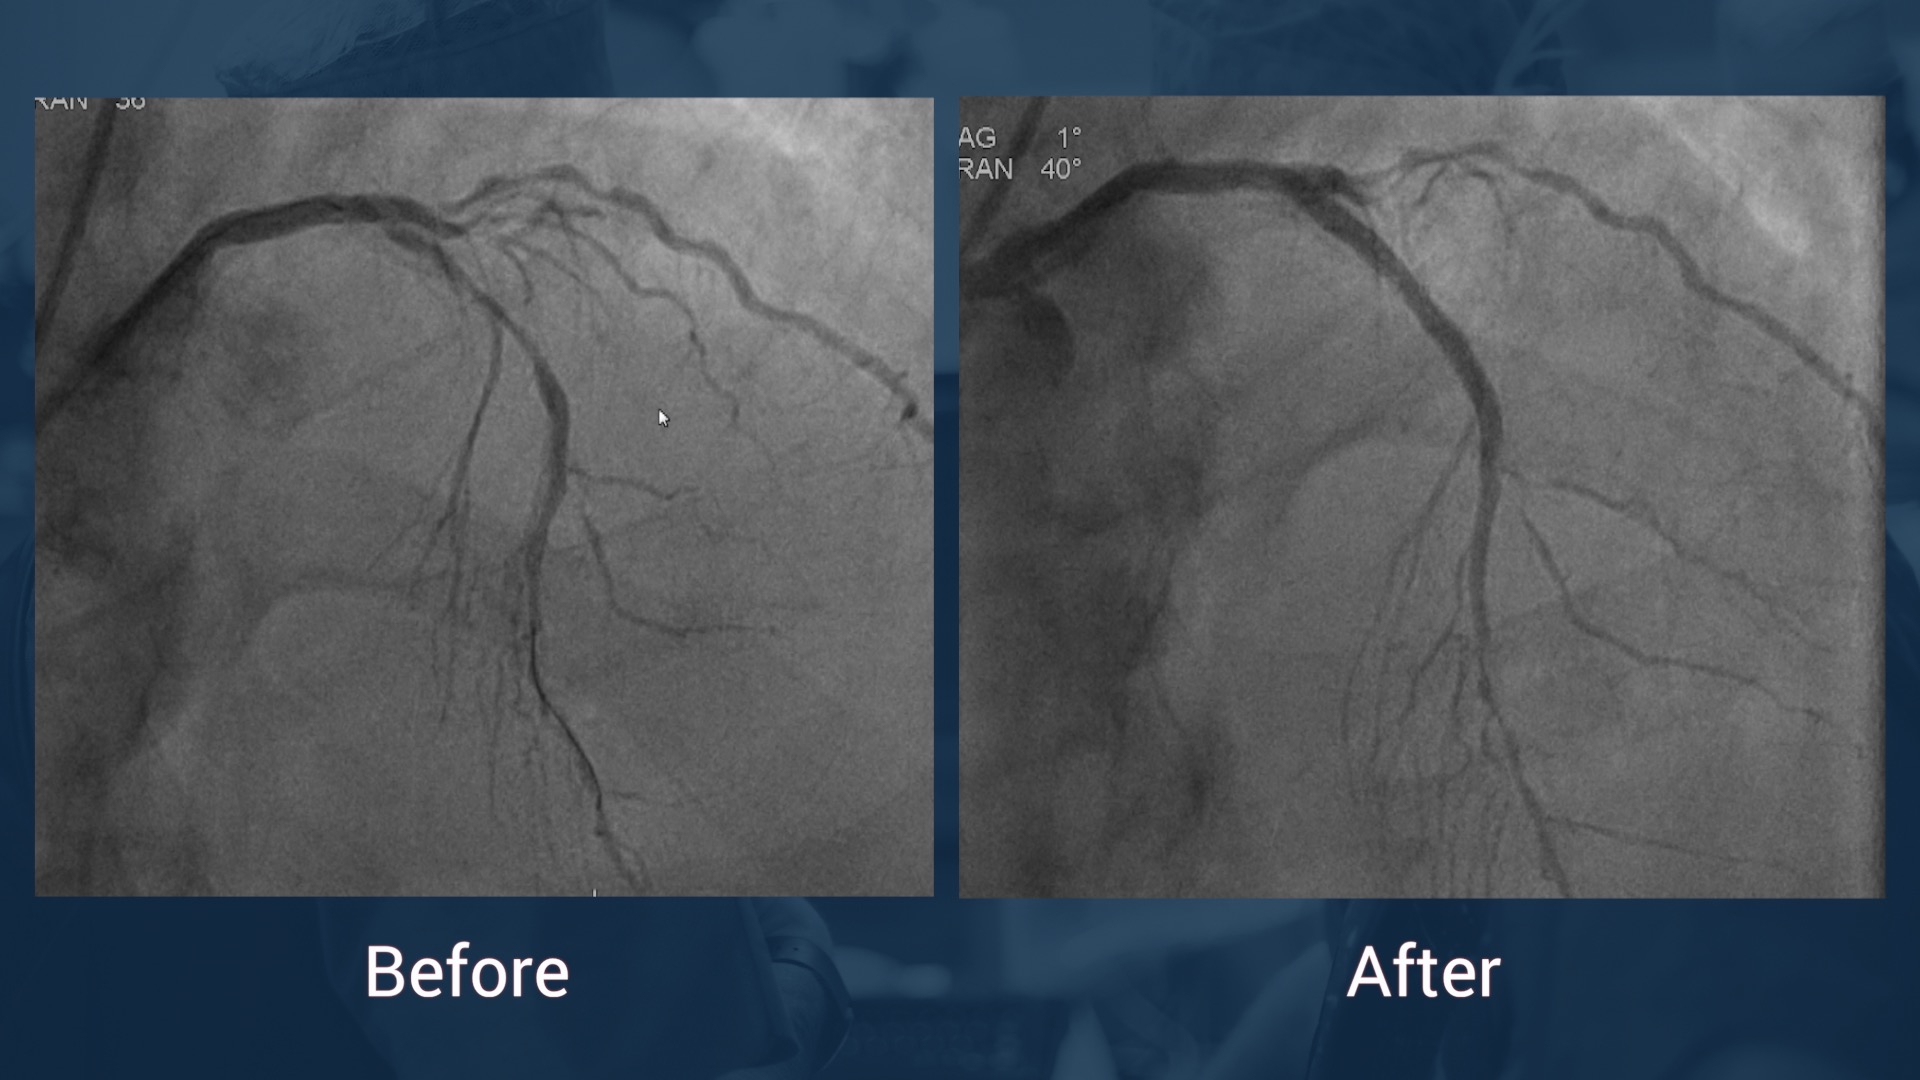

Normal LM

RCA:  CTO of proximal segment with ipsilateral epicardial  collaterals to the PL-branch